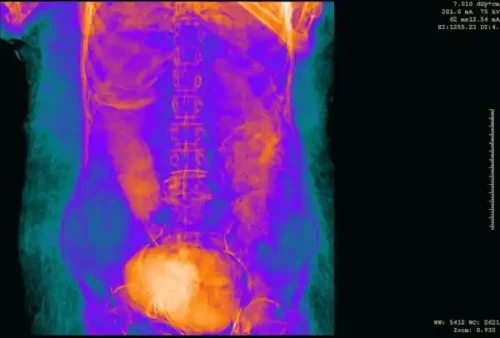

Nonostante il nome maschile trovato sul sarcofago, i ricercatori – durante una prima indagine, anch’essa non invasiva – avevano riscontrato la mancanza dell’organo maschile che veniva mummificato con il resto del corpo. Ulteriori indagini, svolte con la Tac e con i più avanzati strumenti di diagnostica avevano permesso di svolgere virtualmente le bende e di scoprire il corpo di una giovane donna. Altre ricerche hanno consentito di vedere il corpo del bambino e di conoscere le sostanze che furono utilizzate per la mummificazione.

La Tac, attraverso la misurazione del feto – ha consentito di stabilire che la donna era incinta da 28 settimane e pertanto era entrata nel settimo mese di gravidanza. Il settimo mese di gravidanza è infatti compreso tra le 26 settimane+3 giorni e le 30 settimane+4 giorni.